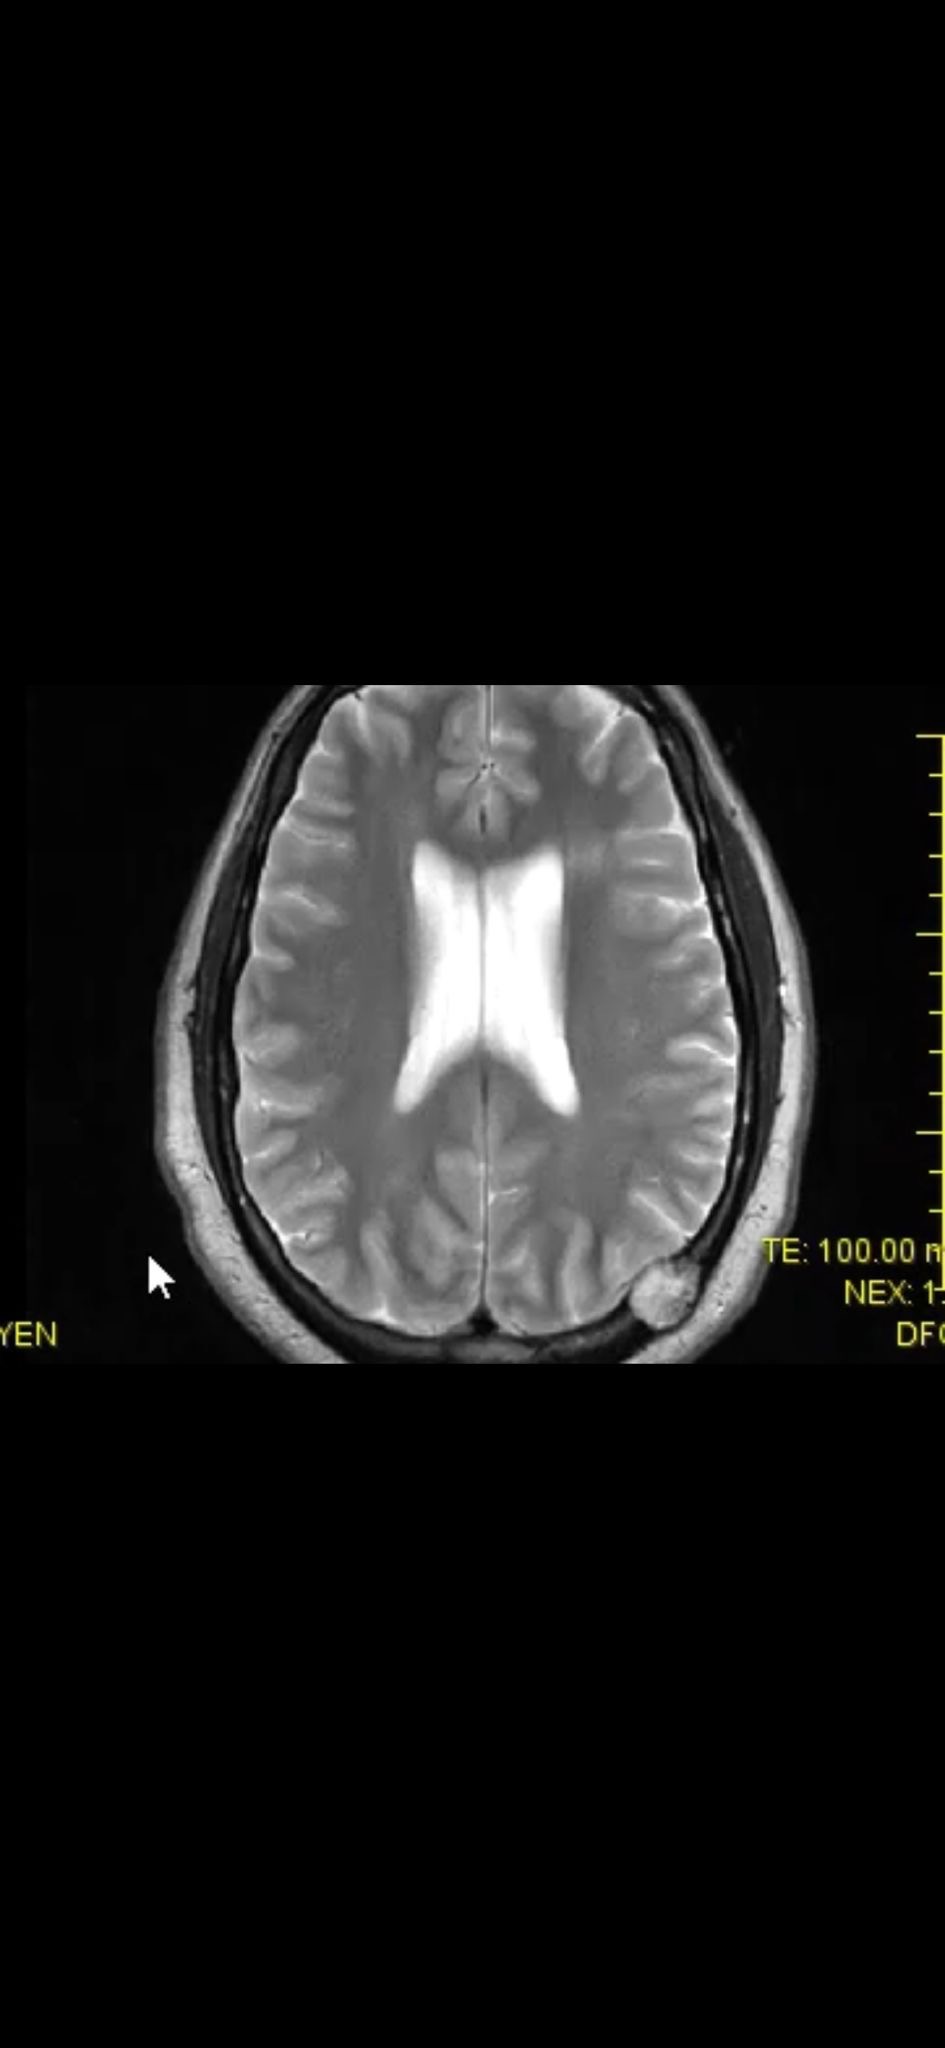

After a brain scan, we learned that there are not one, but two lesions near his brain. In that moment, everything shifted.

Right now, doctors believe the masses have not penetrated the brain itself and are treating him with curative intent. Our next steps include a PET scan and a kidney biopsy at St. Luke’s in the Houston Medical Center, followed by immunotherapy.